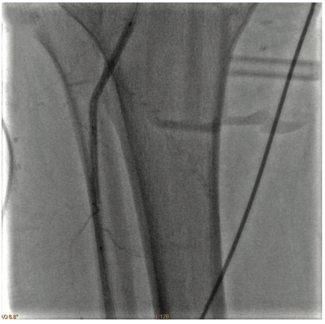

Retrograde, contralateral access was obtained with a 6 French (Fr) 45-inch sheath. Baseline angiography revealed patent iliac, common femoral and profunda arteries.